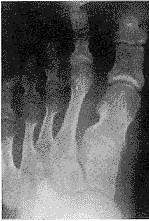

图3 双足跖、趾骨正位像:两侧第1、3、4跖骨变短,尤以第1跖、趾骨粗、短明显;右拇跖、趾关节腓侧软组织内示一条状钙化